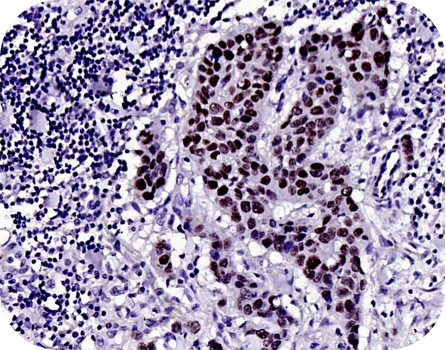

Anti-P53 protein(wt-p53) (bs-0033R)